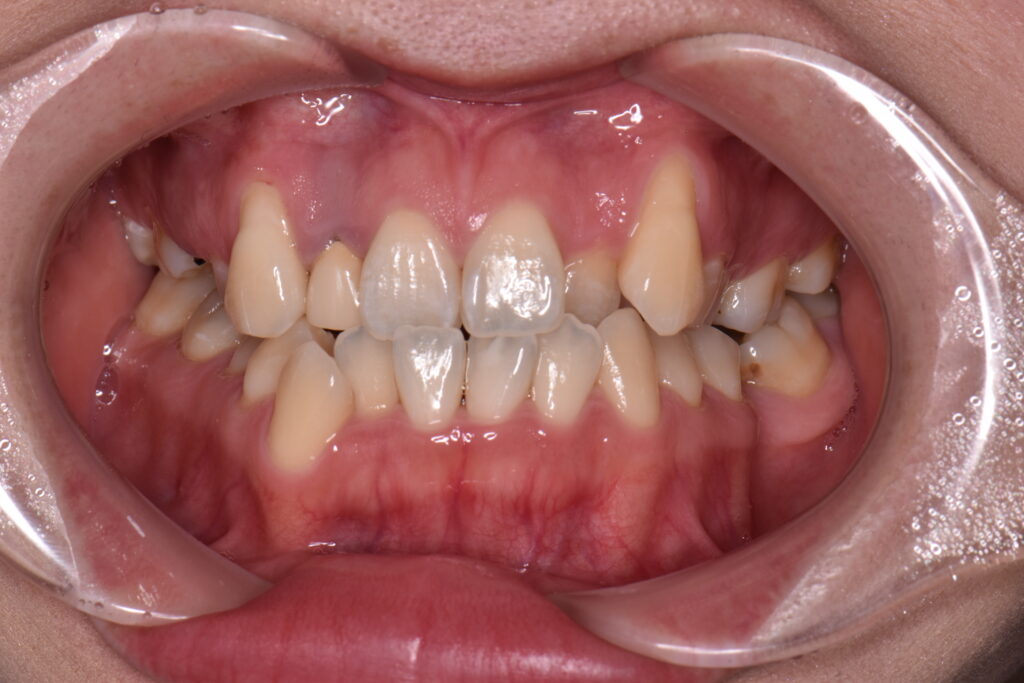

マウスピース矯正で無理をした例

適応を超えてマウスピース矯正を行った場合、

といったトラブルが起こることがあります。

特に、重度の叢生や咬合平面の問題を抱えたケースでは、

途中で ワイヤー矯正への切り替え が必要になることも少なくありません。